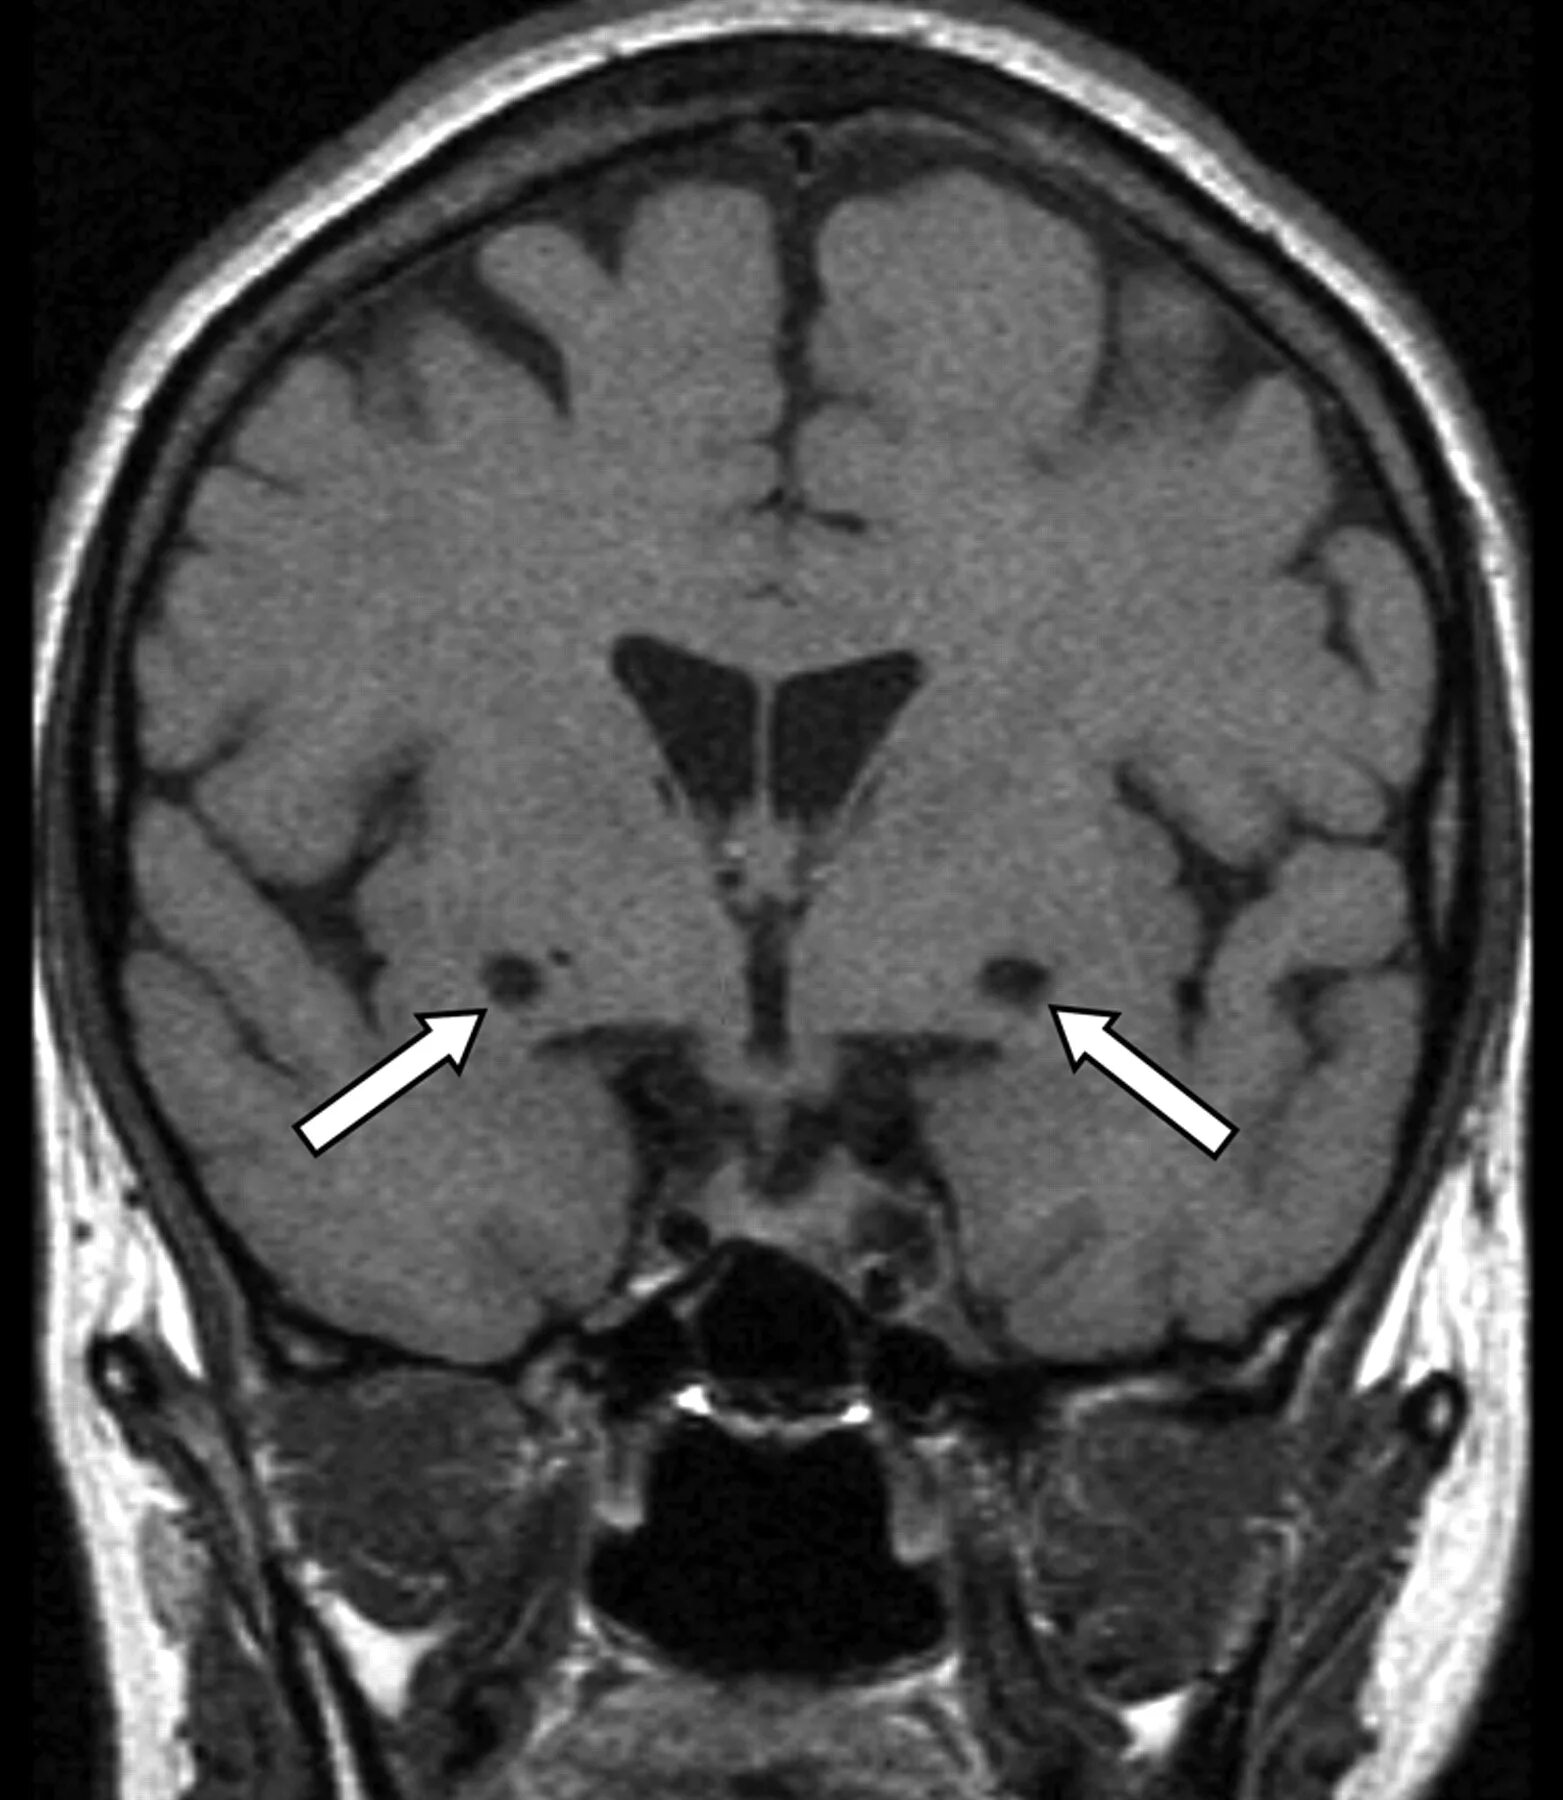

Что значит расширенные периваскулярные пространства